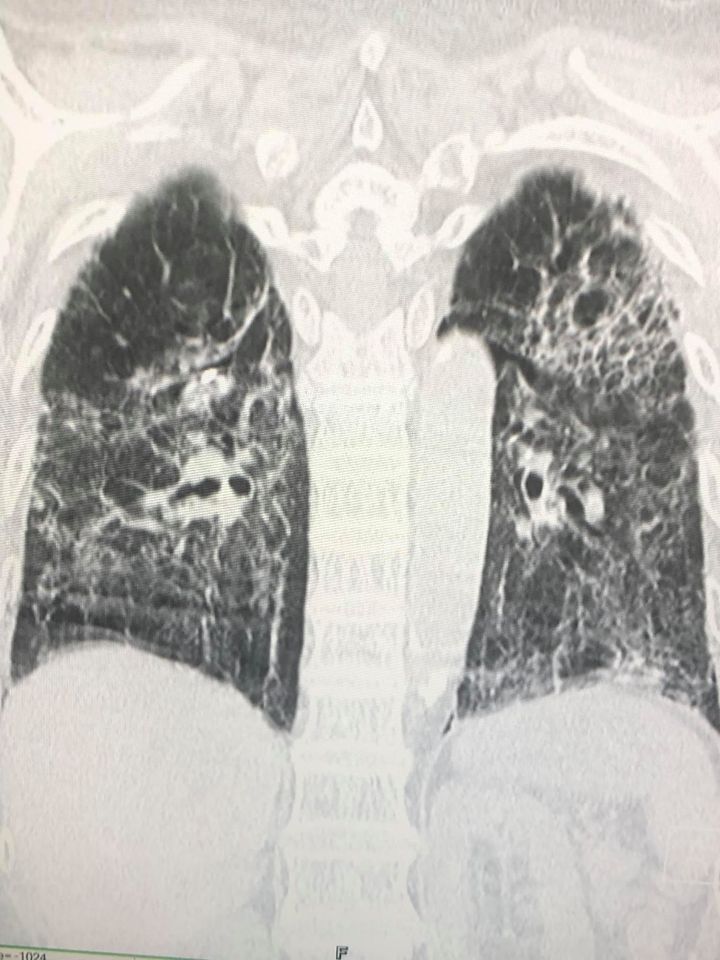

ล่าสุดพบผู้ป่วยไทยปอดรั่วเองทั้ง 2 ข้าง เป็นผลจากการที่เนื้อปอดถูกทำลายโดยเชื้อไวรัสโควิด-19 โดยเป็นผู้ป่วยหญิงไทยอายุ 77 ปี ไม่สูบบุหรี่ ปกติแข็งแรง ไม่มีปัญหาทางปอด ยังไม่ได้ฉีดวัคซีนป้องกันโรคโควิด

- วันที่ 2 กันยายน ทำคอมพิวเตอร์สแกนปอดพบพังผืดทั่วปอดร่วมกับหลอดลมเล็กๆโป่งพอง

- วันที่ 10 กันยายน ได้ทำการผ่าตัดปอดข้างขวาเพราะปอดขวาไม่ขยายตัวเต็มที่ ด้วยการส่องกล้องเข้าไปในช่องทรวงอกข้างขวา พบถุงลมพองโตที่ผิวของยอดปอดข้างขวาด้านบนและด้านล่าง ต้องตัดปอดเฉพาะส่วนนั้นและเย็บปิด ตัดเยื่อหุ้มปอดด้านขวา ใส่แป้งทัลค์ เข้าช่องปอดขวา และผ่านท่อระบายลมข้างซ้าย เพื่อให้เยื่อหุ้มปอดข้างขวาและซ้ายติดกัน

และส่งชิ้นเนื้อปอดตรวจทางพยาธิวิทยา พบว่า เนื้อปอดถูกทำลาย มีทั้งอักเสบและพังผืดทั่วไป มีถุงลมพองในเนื้อปอด ขณะนี้ยังต้องใส่ท่อระบายลมทั้งสองข้าง